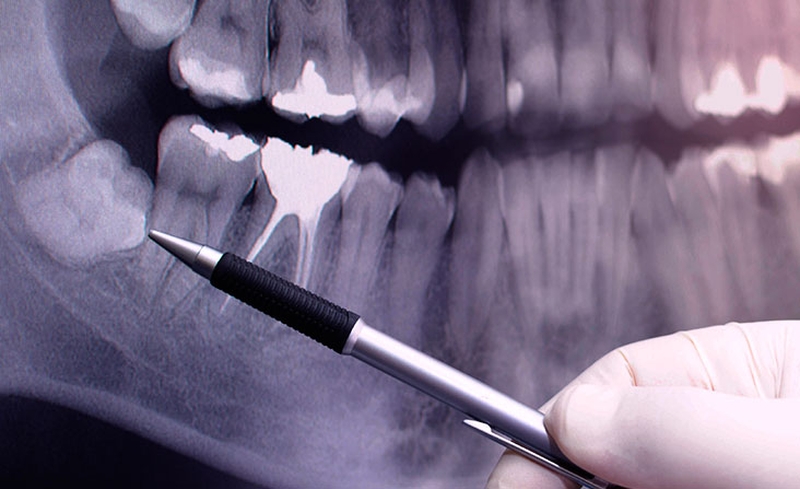

Răng khôn mọc ngầm thường xuất hiện ở hàm dưới, làm xuất hiện những triệu chứng như sưng nướu, hôi miệng và đắng lưỡi… Việc răng khôn mọc ngầm chỉ có thể kiểm tra chính xác bằng việc chụp X quang xương hàm răng.